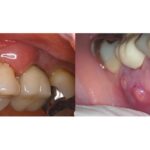

3ヶ月前に、右上奥歯のズキズキとした痛みを主訴に、近くのかかりつけ歯科にて根管治療(抜髄)を開始しました。週1回、10回程度治療を続けていましたが、痛みは引かないどころか強くなる日もあり、ご自身で根管治療について調べたとのことです。その結果、ラバーダム防湿が重要と知ったものの治療を受ける際にはラバーダムが使われておらず、精密な治療を求めて当院を受診されました。

3ヶ月ぐらい前にズキズキとした痛みがあり、近くの歯医者さんで神経を取る処置が必要と言われ、治療を開始しました。初めは「4〜5回ぐらいで終わると思う」と言われていましたが、痛みがずっと変わらず、現在までに10回程度治療を続けています。それでも治らないため、ネットで根管治療について調べて、髙井歯科クリニックに来させていただきました。

ありがとうございます。根管自体はシンプルな形態ですので、おそらく1回で治療は完了できるかと思います。